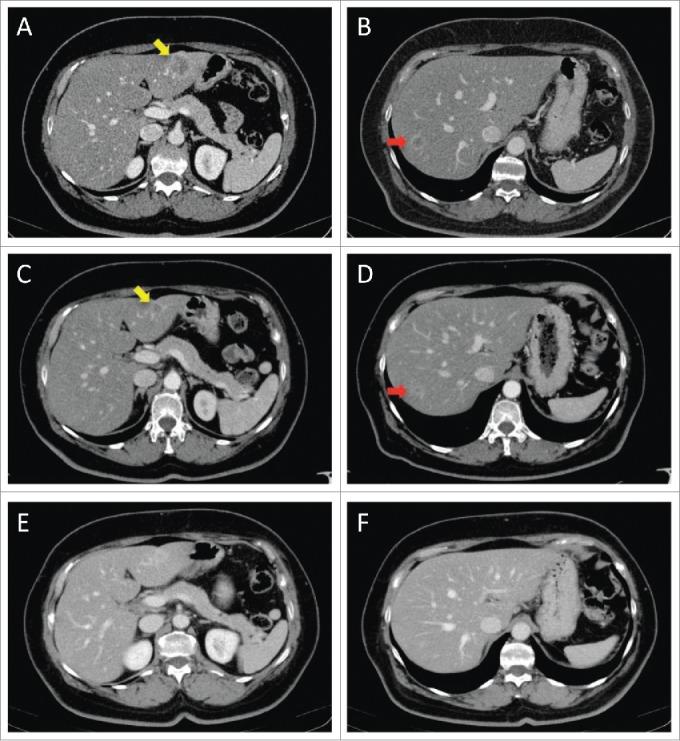

The occurrence of skin metastases is a common event in patients affected by advanced breast cancer, usually associated with systemic disease progression. Here we describe 2 cases of diffuse cutaneous metastases from HER2-overexpressing breast cancer occurring despite a dramatic response in liver and bone, respectively, during treatment with anti-HER2 antibodies Trastuzumab and Pertuzumab. We discuss the reasons for this discrepancy and suggest a possible implication of impaired immune response in the skin. Future research should provide strategies to overcome the induction of immune privilege in the skin in order to avoid discontinuation of effective treatments.

皮肤转移的发生在晚期乳腺癌患者中是常见事件,通常与全身疾病进展相关。在此,我们描述2例HER2过表达乳腺癌的弥漫性皮肤转移病例,尽管在使用抗HER2抗体曲妥珠单抗和帕妥珠单抗治疗期间,肝脏和骨骼分别出现了显著反应,但仍发生了皮肤转移。我们讨论了这种差异的原因,并提出皮肤免疫反应受损可能起到了一定作用。未来的研究应提供策略,以克服皮肤中免疫特权的诱导,从而避免中断有效的治疗。